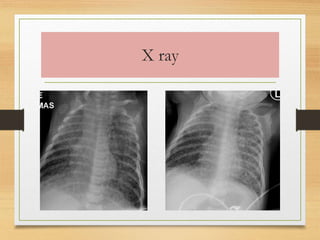

Radiologic diagnosis:

• “Snow storm” appearance (Multiple small lung

nodules 1mm size and above in both lung fields).

Miliary TB

Millets- 1 to 3 mm

X ray